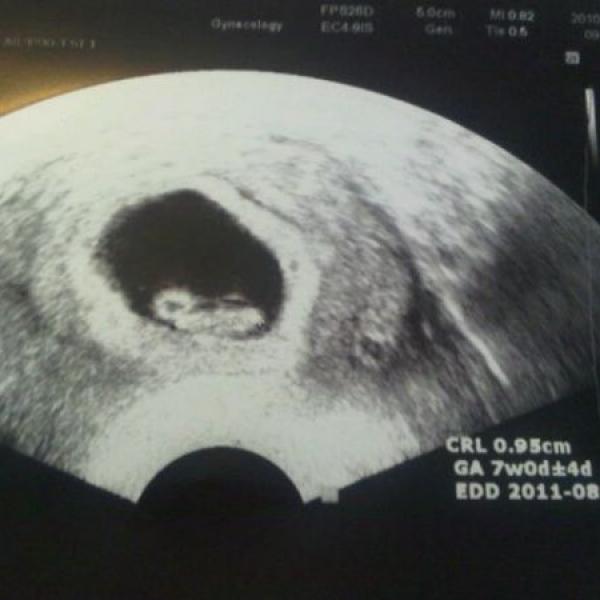

Ahoj maminky, reknu vam, to byl dnes ale den :-) Rano jsem uz nemohla dospat, jak jsem se uz po trech tydnech opet tesila k doktorovi na prohlidku a na to, ze uvidim ten nas maly zazrak.